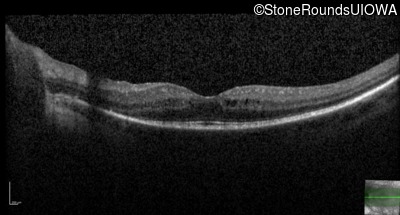

OCT Stack

20/32 -1